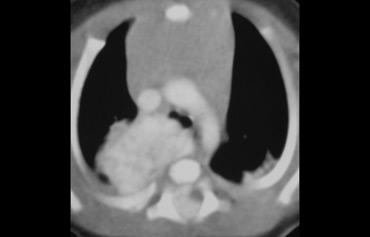

Hãy mô tả hình ảnh bên trái.

Sau đó tiếp tục.

Có nhiều khối ở cả trung thất trước và trung thất giữa.

Giá trị tỷ trọng tương đương tỷ trọng nước.

Các dấu hiệu này gợi ý chẩn đoán hạch bạch huyết dạng nang ở bệnh nhân có bệnh lý di căn.